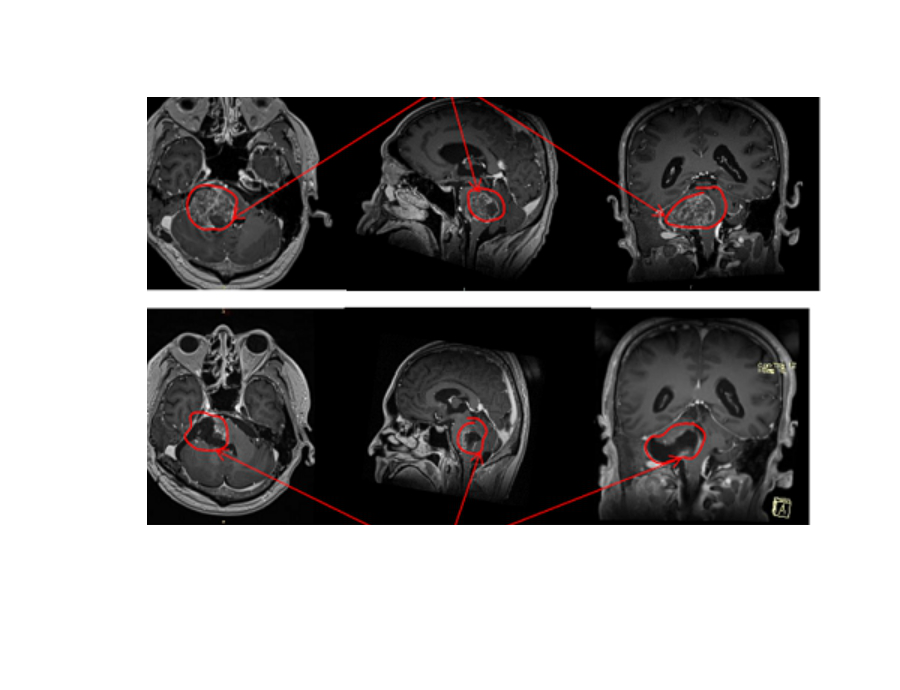

案例1:58岁,刘女士,弥漫性脑干胶质瘤,在INC帮助下,德国INI巴特朗菲教授为其手术切除了95%以上的肿瘤。

德国手术前后影像资料对比